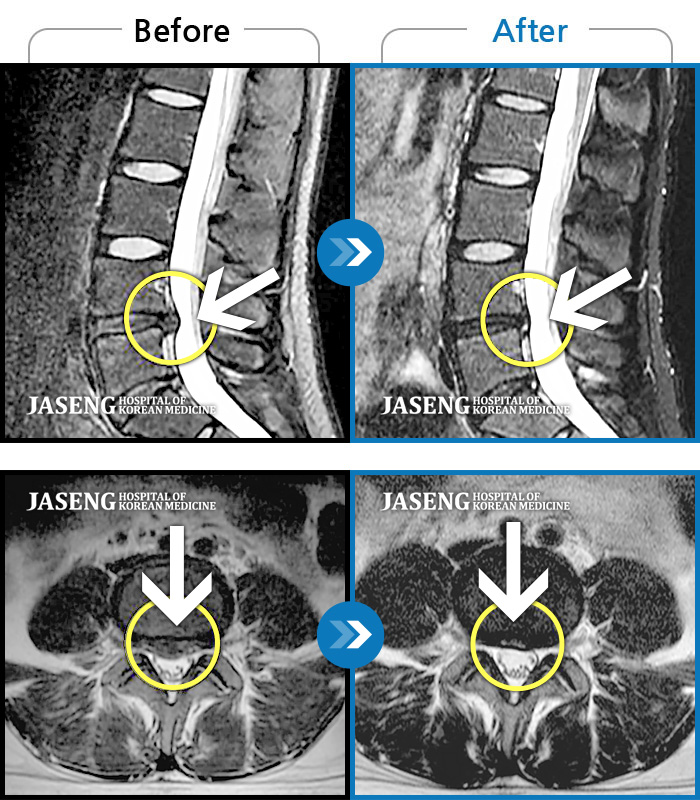

40대 초반 여성 환자인데요,, 처음 선생님 뵈었을 때에 1번,4,5번허리디스크 증상도 증상이지만,

본인 나이에 비해서 10~15년정도 퇴행이 많이 되어있어서 전체적으로 관리가 많이 필요하다고 설명해주셨구요,,

그당시 원장님진료실에서 보았던 저의 엠알아이사진이 아직도 생생히 기억이 납니다 ^^

뼈부분의 색이 왜저렇게 검냐고 여쭈어 보았더니, 말씀주신데로 "퇴행이"많이 되어서 그렇다고 설명해주시면서,,

그렇다고 당장 크게 머가 안좋거나 그런건 아니고,, 퇴행된 뼈자체를 새것으로 되돌릴수는 없지만,,

꾸준히 치료받으면서 관리만 잘한다면 건강한 뼈를 가진 사람과 동일하게 건강한 생활 충분히 가능할수 있다고,, 긍정적으로 말씀을 주셨어요...